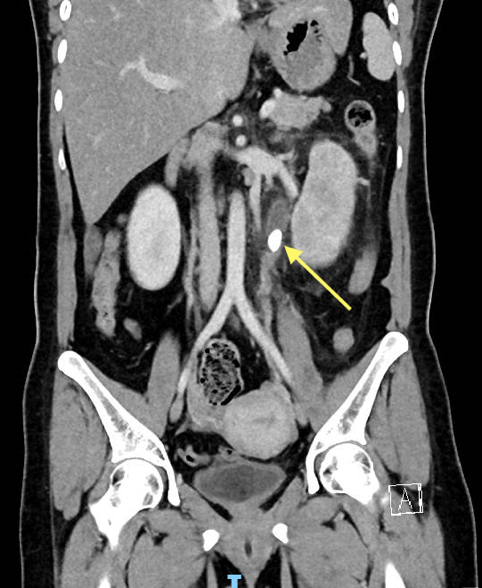

Once diagnosed, the size and location of the stone are important in guiding the options for treatment.